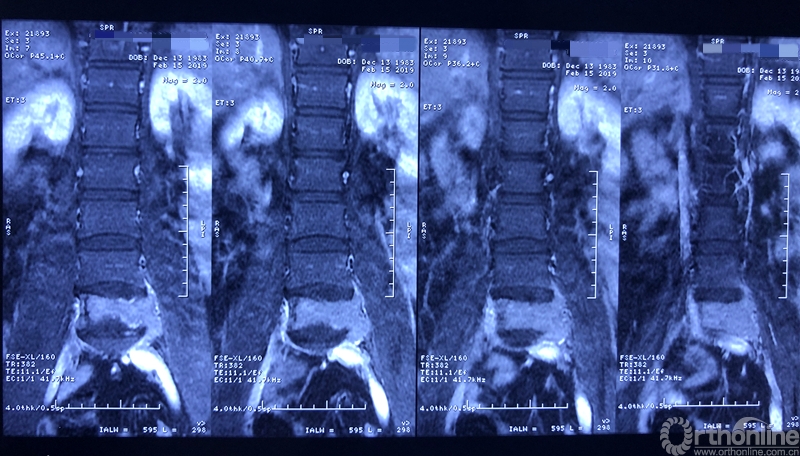

据介绍,患者为39岁男性,在一年前开始出现腰部反复疼痛的症状,休息下后疼痛还可以缓解,当时并未引起患者重视。过年后感觉疼痛加重,赴当地医院检查。核磁共振显示腰椎上长了一个鹅蛋大小的肿瘤,不偏不倚地侵蚀在第五节腰椎上,正是腰椎和骨盆连接部位附近。于是患者来同济医院骨科就诊。

就诊前CT

通过对患者详细的身体检查、穿刺活检和综合评估后,确诊患者是腰椎骨巨细胞瘤,第五腰椎破坏70%以上,邻近软组织也有破坏。这种肿瘤属于交界性的有恶性倾向的良性肿瘤,若不彻底切除,患者疼痛会逐渐加剧,甚至因骨质坍塌而瘫痪,若肿瘤细胞转移更会危及生命。若是能在早期尽快彻底、完全地切除肿瘤及被侵蚀椎体,病人才很可能完全战胜肿瘤。